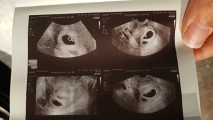

Ik voelde niets en had de hoop al opgegeven. Ik begon het een plaatsje te geven dat Ayline een enig kind zou blijven. En toch, uit de bloedanalyse bleek dat ik zwanger was, joepiiiieee. Blij, maar toch op onze hoede wachten we de tweede bloedanalyse af, waarop mijn gynaecoloog zei: “het is duidelijk dat je heeeel zwanger bent, kom volgende week maar langs voor echo”. Het gaan er toch geen twee zijn, wat is de kans? En toen, op de echo, zag ik onmiddellijk 2 verschillende vlekjes en iets later ook 2 hartjes kloppen.

De zwangerschap verliep in het begin vlotjes, beetje misselijk maar niet veel, geen kwaaltjes en 12 weken echo en NIPT waren goed. Het werd een jongen en een meisje! Enkel onze jongen zijn placenta lag voor de baarmoederhals en rond 20 weken zwangerschap vond de gynaecoloog dat de kindjes wat te klein waren. We maakten ons geen zorgen daar onze dochter op 40 weken geboren is met 2460 gram.